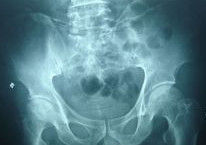

⑤X線表現。骨紋理細小或中斷,股骨頭囊腫、硬化、扁平或塌陷。

骨壞死的發生,演變和結局,有其規律性病理過程,即壞死發生一死骨被吸收一新骨形成。X線表現不管壞死範圍大小,單發或多發,都是這一過程的縮影。股骨頭壞死的X線分期方法很多,但我們一般採用Arlet,Ficat和Hageffard的5期分法:

Ⅰ期(前放射線期)此期約有50%的患者可出現輕微髖痛,負重時加重。查體:髖關節活動受限,以內鏇活動受限最早出現,強力內鏇時髖關節疼痛加重。X線顯示:可為陰性,也可見散在性骨質疏鬆或骨小梁界限模糊。

Ⅱ期{壞死形成,頭變扁前期)臨床症狀明顯,且較I期加重。X光片顯示:股骨 頭廣泛骨質疏鬆,散在性硬化或囊性變,骨小梁紊亂、中斷,部分壞死區,關節間隙正常。

Ⅲ期(移行期)臨床症狀繼續加重。X光片顯示:股骨頭輕度變扁,塌陷在2mm以內,關節間隙輕度變窄。

Ⅳ期(塌陷期)臨床症狀較重。下肢功能明顯受限,疼痛多緩解或消失,患肢肌肉萎縮。X光片顯示:股骨頭外輪廓和骨小梁紊亂、中斷,有半月征,塌陷大於2mm,有死骨形成,頭變扁,關節間隙變窄。

Ⅴ期(骨關節炎期)臨床症狀類似骨性關節炎表現,疼痛明顯,關節活動範圍嚴重受限。X光片顯示:股骨頭塌陷,邊緣增生,關節間隙融合或消失,髖關節半脫位。正確的診斷和分期,對決定治療方法和治療效果有密切的關係。早期治療可防止骨壞死的股骨頭塌陷。如果在X線上發現或懷疑有骨壞死,可繼續做磁共振(MRI)或CT掃描。但以上兩種檢查費用較高,故一般建議患者拍骨盆正位X線片即可,或加拍雙側髓部X線片,屈髖至90°外展位髖關節片。